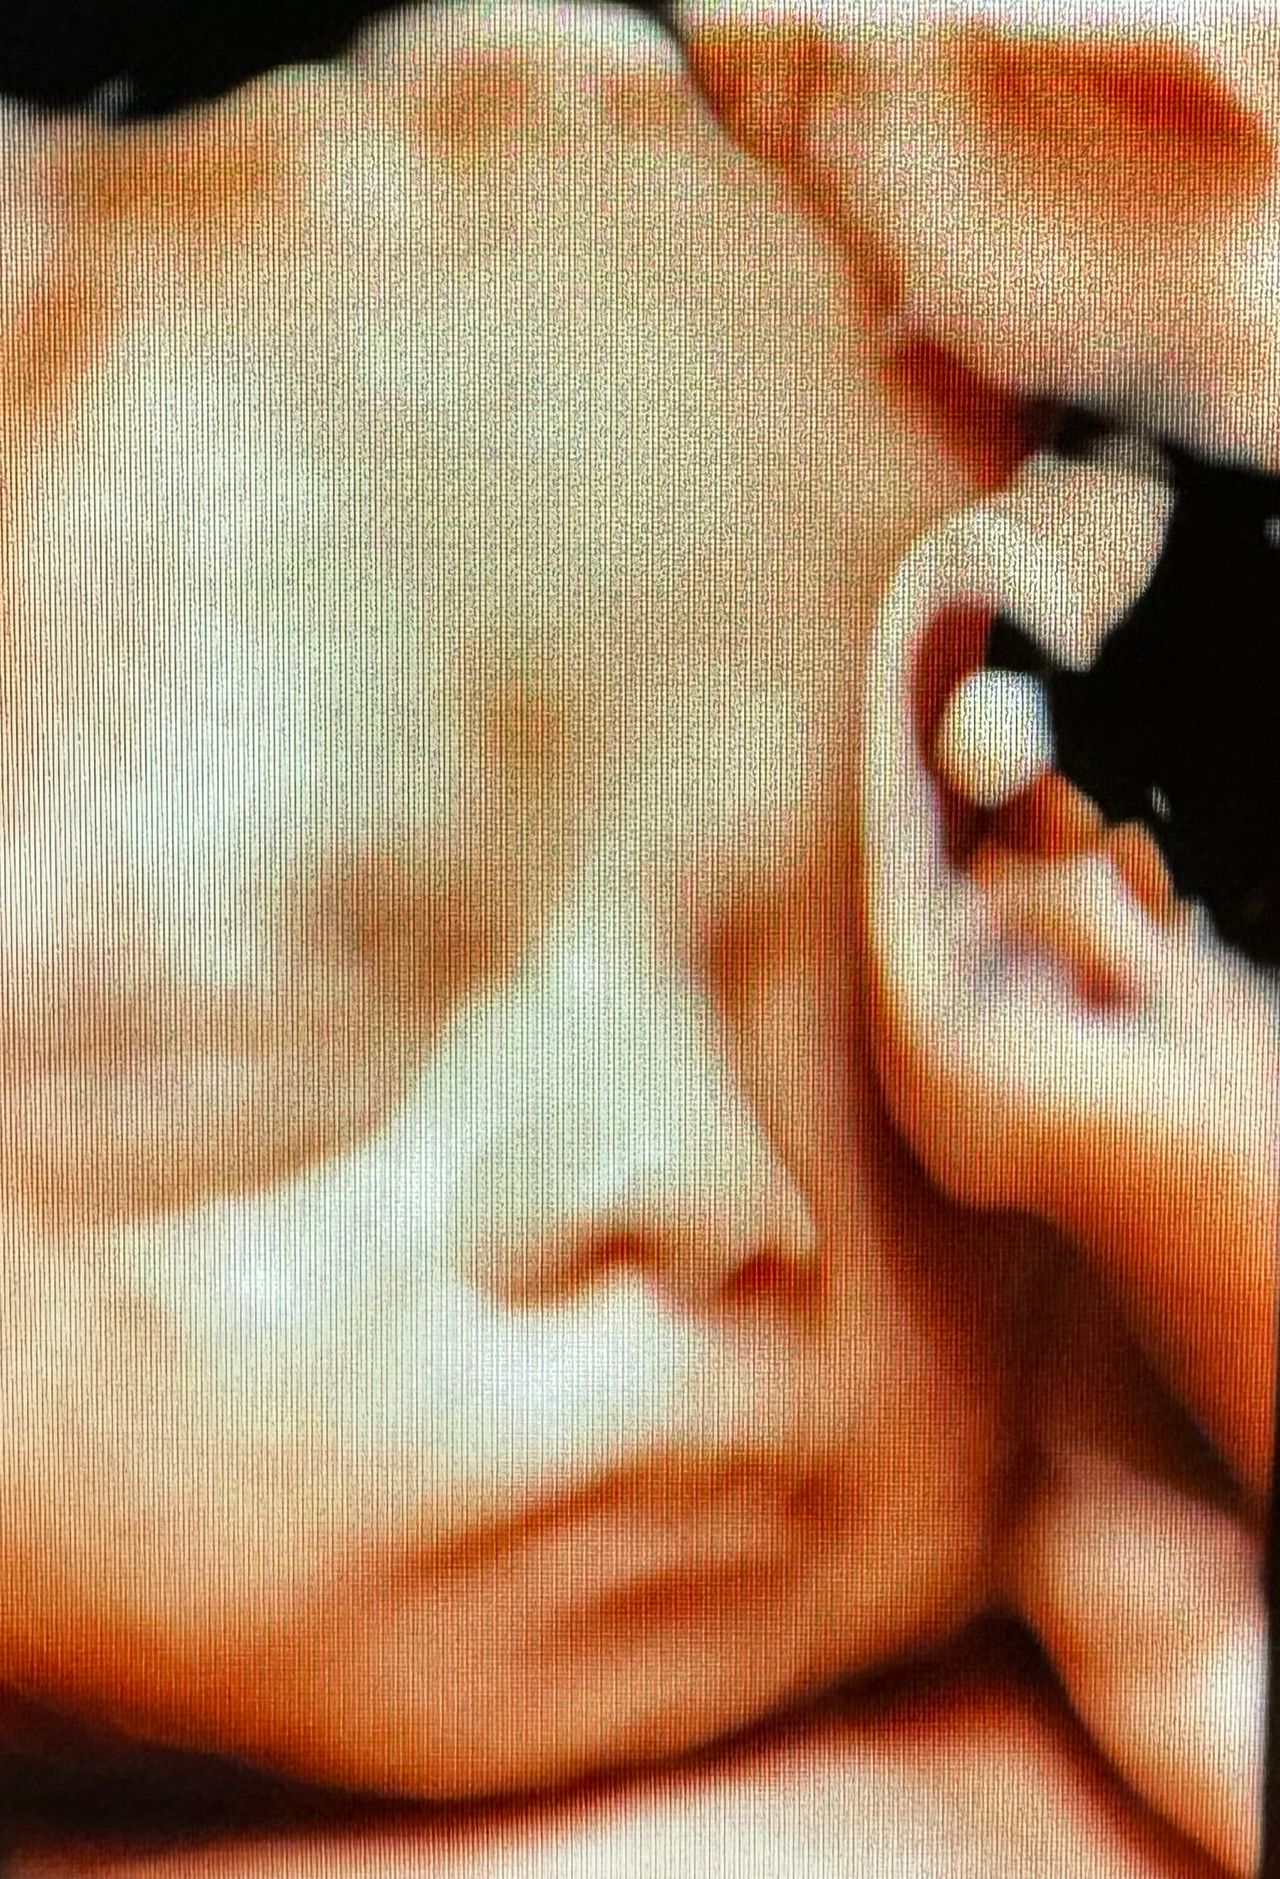

Ultrasonido 4D

Que podríamos decir de el que no se haya dicho antes, su gran trabajo y dedicación por cada paciente.

Mi esposa y yo ambas mujeres buscamos un embarazo desde el inicio del tratamiento fue el más dedicado, empático y detallado cada medicamento nos explico para que era y como funcionaba, gracias a la fe y a su gran trabajo como médico hoy tenemos a nuestra princesa en nuestros brazos ya de 1 semana. Estamos muy agradecidas de haberlo encontrado y de haber puesto toda nuestra fe y salud en sus manos..

Excelente doctor, estamos muy contentos porque en cada cita nos explica con claridad y es muy atento a nuestras dudas. Actualmente llevo mi embarazo con él después de buscar bebé.